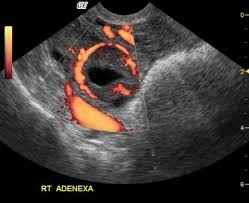

Transabdominal or transvaginal ultrasound findings suggestive of ectopic pregnancy:

The ring of fire is the classic finding on ultrasound, and describes the increased vascular flow to the adnexa when color Doppler is applied. Note: Similar findings occur with a well-developed corpus luteum, so be careful

No intrauterine pregnancy. Remember that a pseudogestational sac may be seen in cases of ectopic pregnancy.